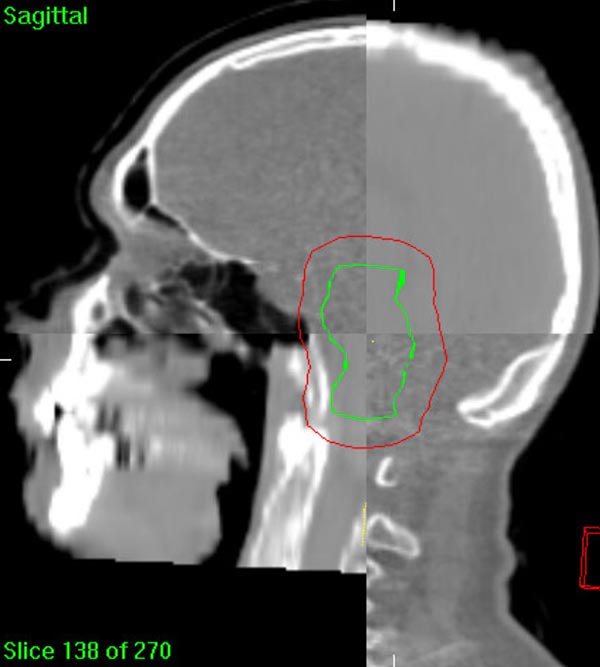

The 3-D high-quality images taken at the time of your treatment can be studied against your previous CT scans precisely and promptly to ensure that the doctors are treating your tumor as accurately as possible while greatly limiting any exposure to healthy tissue in the area.

Elekta Synergy® provides unparalleled clinical assurance to more aggressively treat tumors while keeping damage to surrounding healthy tissues to a minimum. Elekta Synergy®‘s precision accuracy reduces or eliminates the use of markers because clinicians can view soft tissue using Elekta Synergy®‘s VolumeViewTM. The low-dose imaging proficiency helps minimize the side effects of radiation therapy by decreasing the margins previously set to account for the unpredictability of target location, movement, and dimensions.